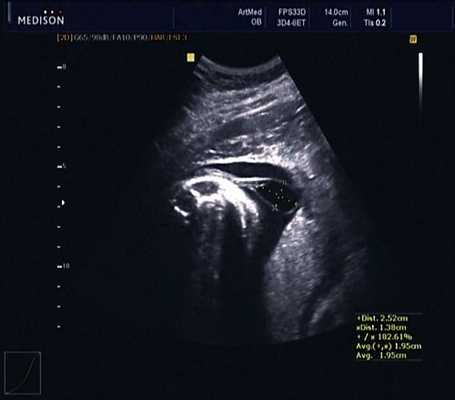

В 30 нед фетометрические показатели плода соответствовали сроку беременности. Сколиотическая деформация позвоночника сохранялась. Дополнительно выявлена оболочечная грыжа, исходящая из грудного отдела позвоночника, в области деформированных позвонков. Грыжа представляла собой стебельчатой формы образование с суженной ножкой (рис. 7, 8). Концевая часть ее была расширена в виде петли и заполнена анэхогенным содержимым (ликвором), которое отчетливо дифференцировалось на фоне "мутных" околоплодных вод (рис. 9). Таким образом, диагноз был уточнен: spina bifida - менингоцеле.